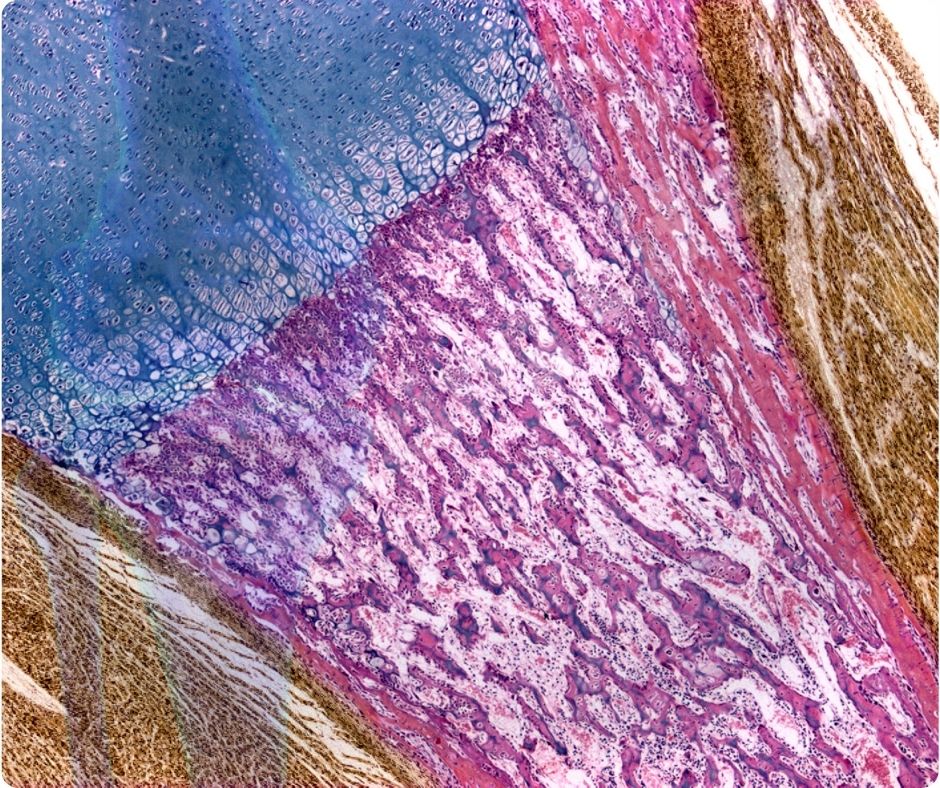

일본 연구진이 진행한 2008년 연구에 따르면, 오징어 연골에서 추출한 E형 콘드로이친은 조골 세포의 성장을 촉진하는 데 매우 효과적입니다. 이 연구는 Journal of Cellular Physiology에 게재되었으며, E형 콘드로이친이 다른 유형에 비해 훨씬 적은 농도에서도 조골 세포의 성장을 유의미하게 촉진한다고 보고했습니다.

콜라겐 축적 촉진

콜라겐은 관절 연골과 뼈의 중요한 구성 성분입니다. 오징어 연골에서 추출한 E형 콘드로이친은 조골 세포에 의한 콜라겐의 축적을 강화하고, 히드록시프롤린 함량을 증가시키는 것으로 나타났습니다. 이는 연골과 뼈 건강을 유지하는 데 큰 도움이 됩니다.

파골 세포 분화 억제

또 다른 연구에서는 E형 콘드로이친이 파골 세포의 분화를 억제하는 것으로 나타났습니다. 이는 골다공증 예방에 도움이 될 수 있으며, 뼈의 결함을 치료하는 데 효과적일 수 있다는 가능성을 시사합니다.